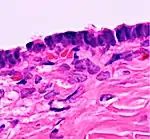

Histopathology

In case an ovarian cyst is surgically removed, a more definite diagnosis can be made by histopathology:

| Type | Subtype | Typical microscopy findings | Image |

| Cystadenoma | Serous cystadenoma | Cyst lining consisting of a simple epithelium, whose cells may be either:[21]

|

|